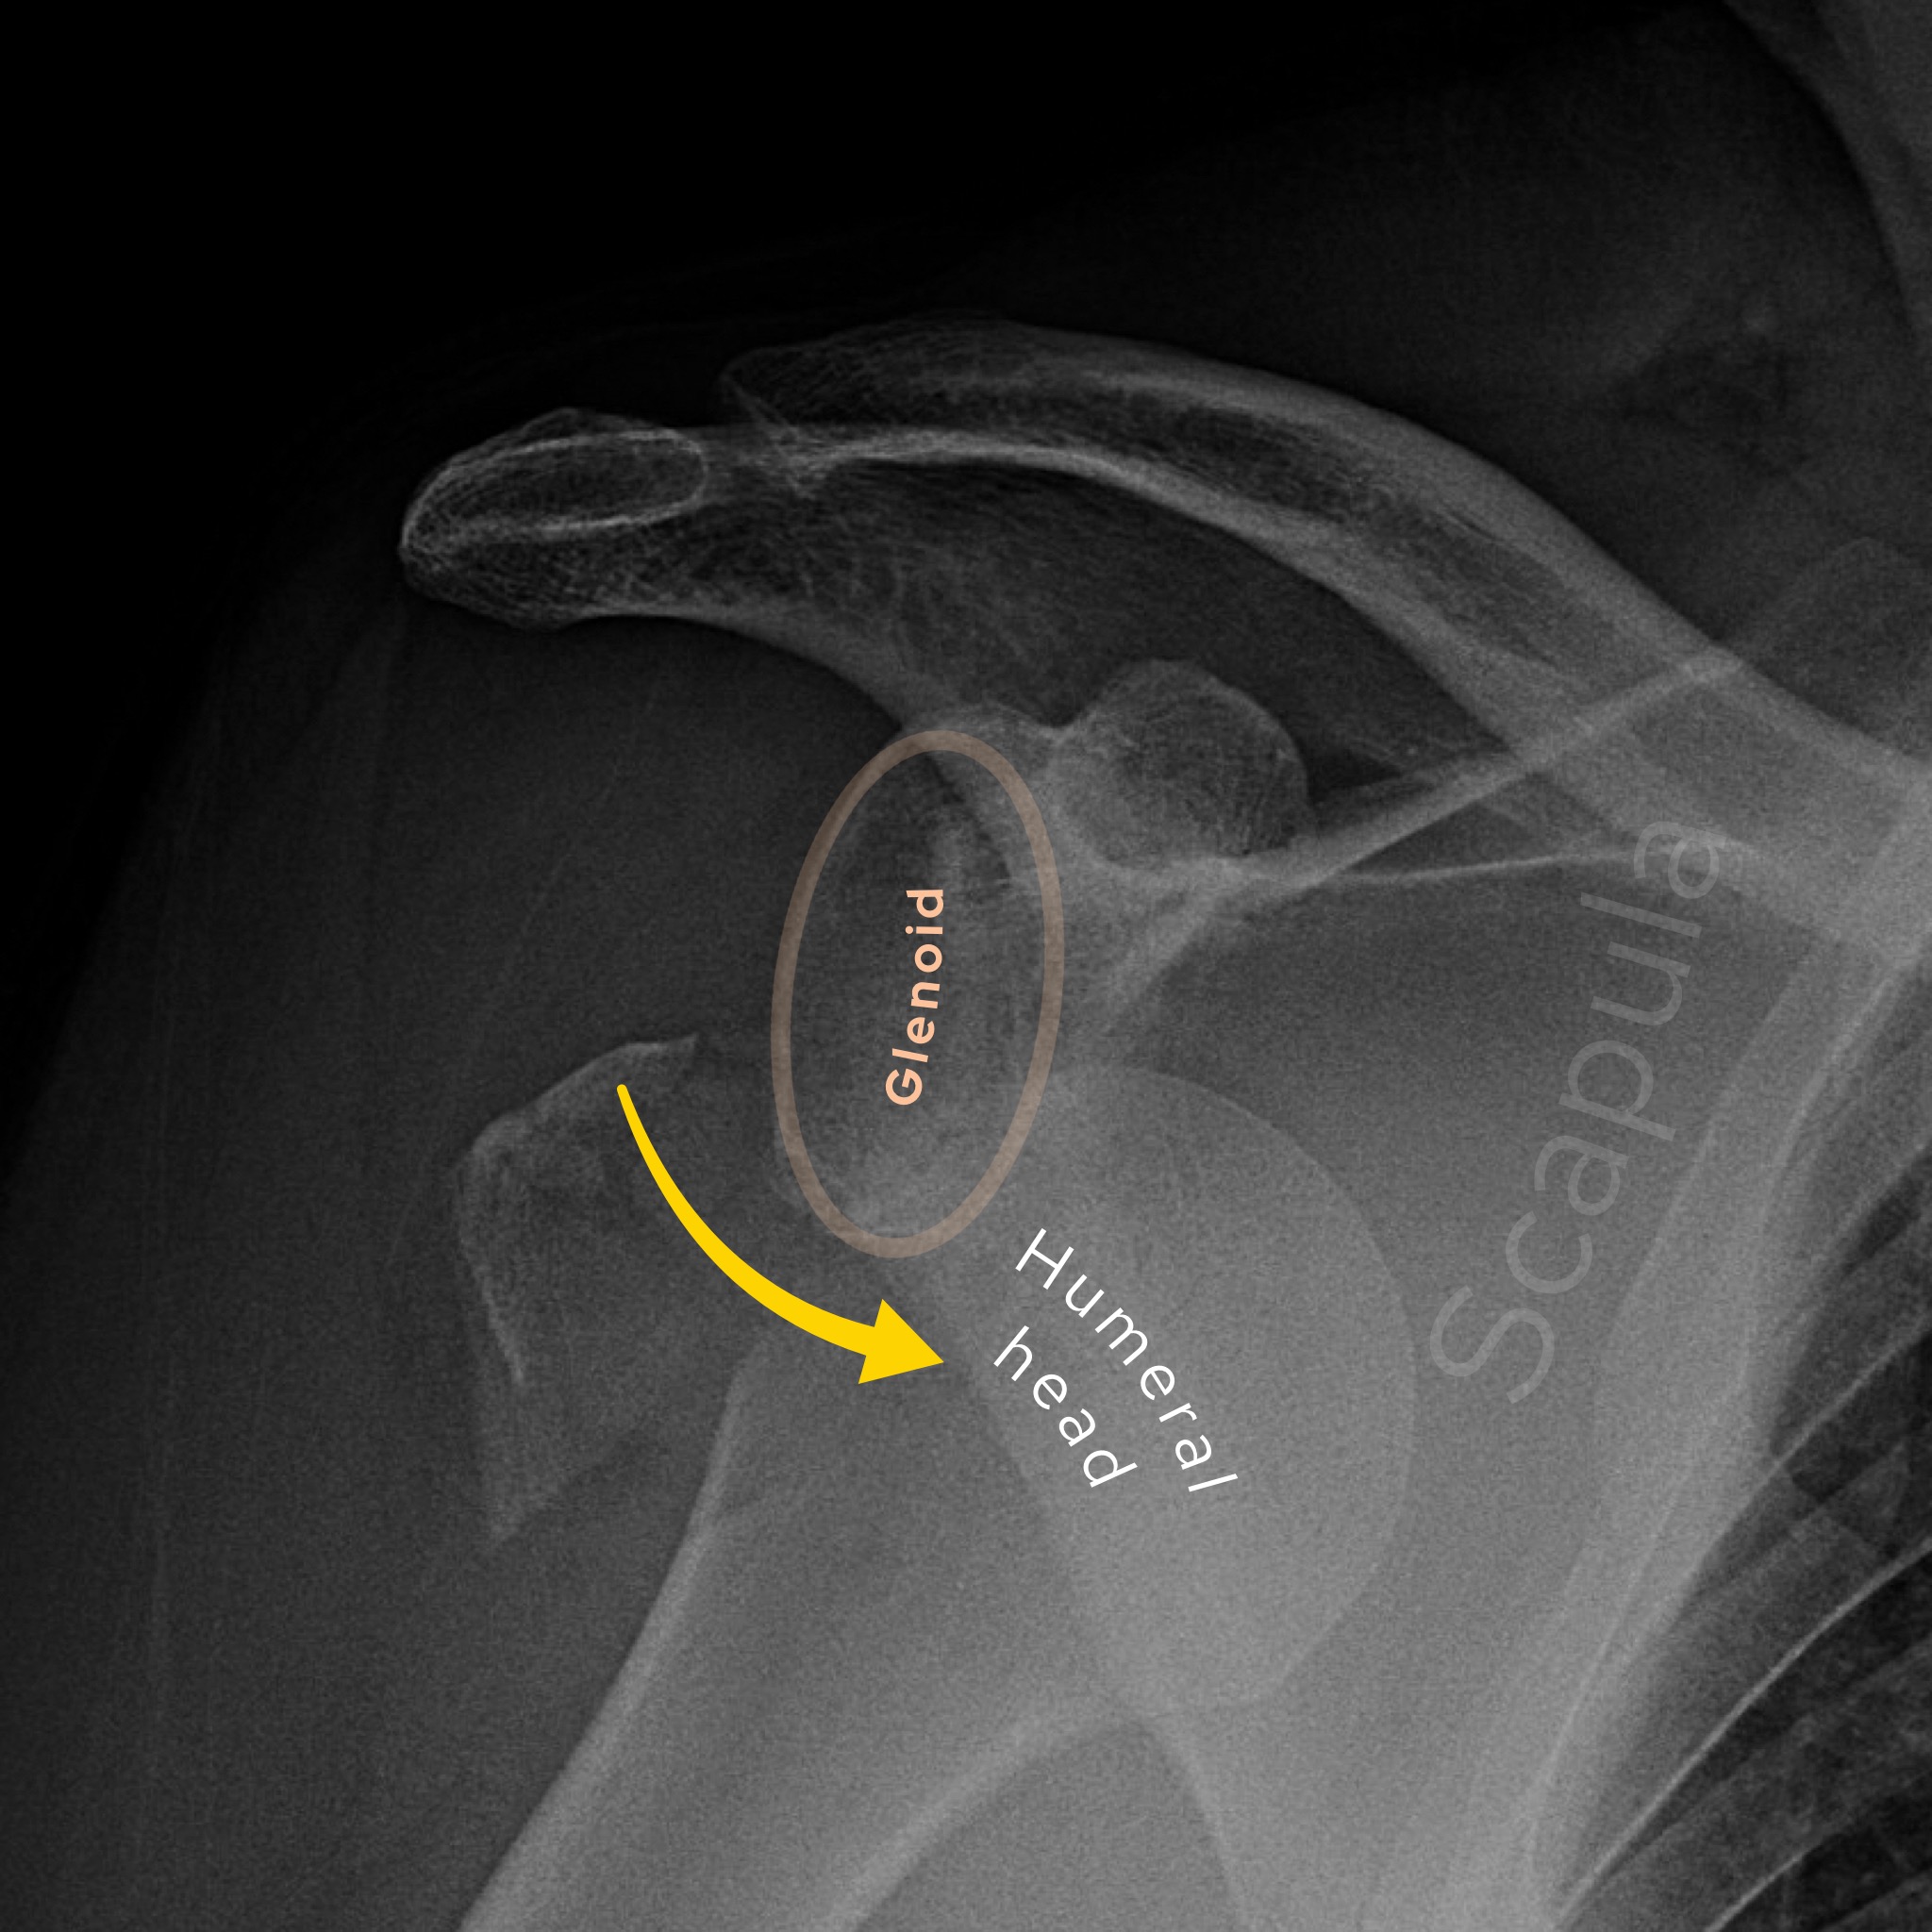

Case 3

A male in his 80s presents to the Emergency Department with shoulder pain and deformity after an episode of trauma. What is the diagnosis?

Choose from one of the following options: